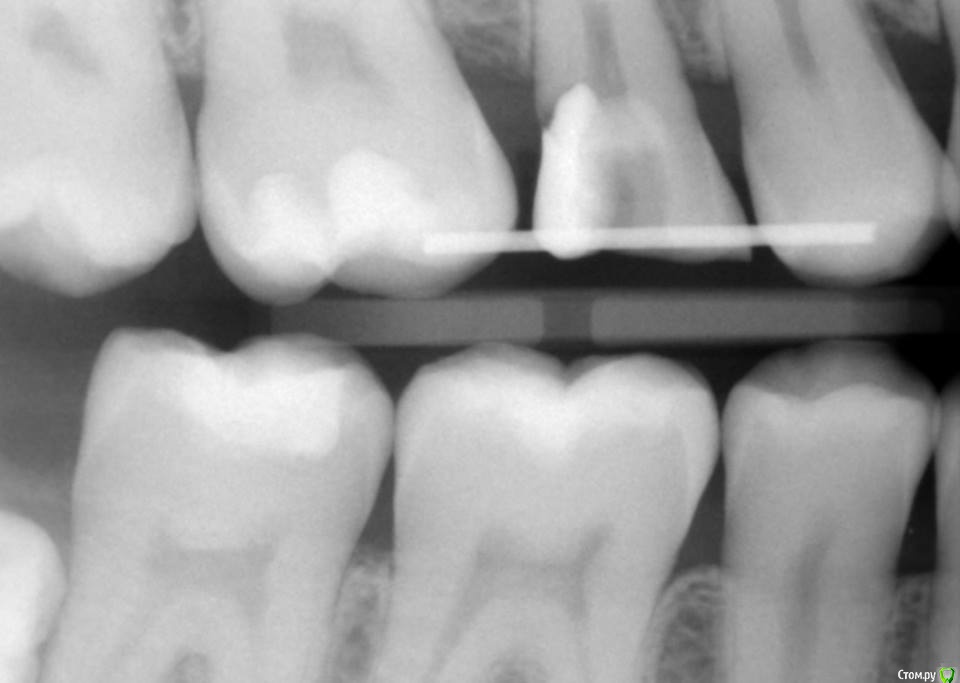

Kolchanov Опубликовано 23 июня, 2015 Поделиться Опубликовано 23 июня, 2015 Экструзия одиночного зуба для получения хоть какого-нибудь феррула. Подозреваю, что процедура не очень сложна и вполне модет быть освоена простым терапевтишкой, т.е. мной. Был бы очень благодарен, если бы кто-нибудь накидал своих мыслей по этому поводу, а еще лучше и фоток. И, конечно же, перечисление материалов. В одной из клиник, где я работаю, делают так иногда.После удаления штифтового зуба имеем поддесневой дефектhttp://s010.radikal.ru/i311/1506/49/4f3a03a5b53b.jpghttp://s010.radikal.ru/i313/1506/55/c752a532f478.jpgПациентка пожелала зуб сохранить. Теперь его тянут. И пятерочку еще в придачу.http://s014.radikal.ru/i327/1506/75/e9897bfb0e24.jpghttp://i024.radikal.ru/1506/99/1f1453b881ef.jpghttp://s017.radikal.ru/i434/1506/ea/caf4284659b4.jpghttp://s018.radikal.ru/i522/1506/ae/b2b54bddcdb8.jpghttp://s015.radikal.ru/i331/1506/7c/0efe752f8c35.jpgПока ничего сложного не вижу.У меня сейчас есть похожий случай. Но, послать в Москву... Не поедут. А на местного ортодонта как-то надежды мало. Я потом залью сюда фотки со своими мыслями. Может кто что присоветует...Спасибо! 1 Ссылка на комментарий

krokomot Опубликовано 23 июня, 2015 Поделиться Опубликовано 23 июня, 2015 Нет, к брекетам отношусь весьма ровно. За ссылку спасибо! Метод с кручком мне не нравится. Его вытаскивать потом надо. Так и нафиг он тогда нужен, если все равно проволоку к зубам клеить. Проще уж тогда зацепы эти из композитария сделать. Спилить их куда проще.На сколько зубов брекеты клеить для экструзии той же пятерки? 6го и 4го хватиткрючек не обязательно сам принцип. Я думаю нужно не меньше 2-х с каждой стороны чтоб не поехали, можно и по одному , но нужно чтоб 100% сила была вертикальной, а это достижимо, если проволка на соседних зубах крепится не жестко, то есть при деформации прогиба она не должна смещать соседние зубы в сторону дефектаhttp://s017.radikal.ru/i410/1506/75/b2ecfc92b62d.pngда и следите чтоб аппроксимальных контактов небыло, иначе все затормозится)) Ссылка на комментарий

Kolchanov Опубликовано 25 июня, 2015 Автор Поделиться Опубликовано 25 июня, 2015 (изменено) Вопрос такой - при ортоэкструзии обязательно нужно каждую неделю "подрезать" круговую связку? По теме есть вот такой кейс, автора к сожалению не помню.Это Григория (ForestDent) кейс. Связку надо обязательно резать, чтобы без кости вытягивался. Изменено 25 июня, 2015 пользователем Kolchanov 1 Ссылка на комментарий